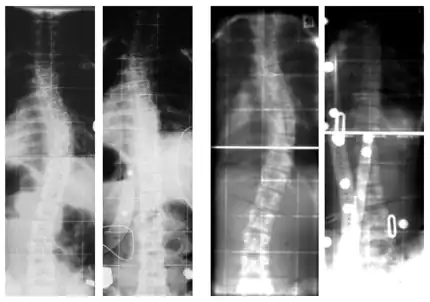

Röntgenbilder in der Frontal- und Sagittalebene

Korrektur von 56° auf 27° Cobb (52 % Primärkorrektur)

Links: von 39° auf 12° Cobb (69 % Primärkorrektur)

Rechts: von 38° auf −14° Cobb (Überkorrektur[22])